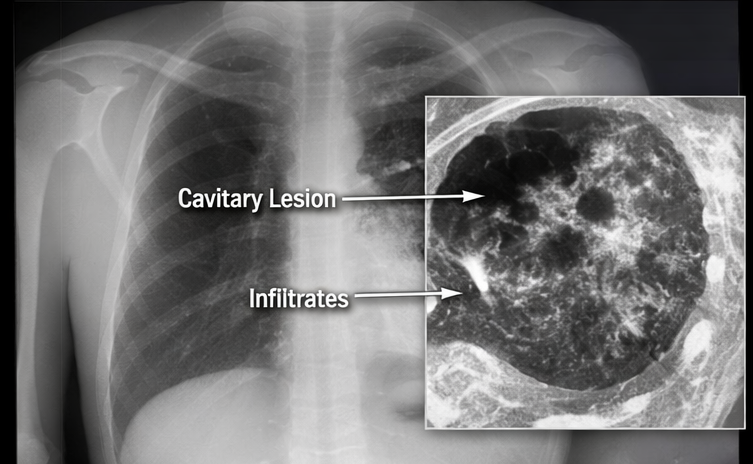

Chest radiography revealed right upper lobe consolidation with cavitary lesions and fibronodular infiltrates. High-resolution computed tomography of the chest demonstrated thick-walled cavitary lesions with surrounding tree-in-bud nodularity and centrilobular micronodules, consistent with active pulmonary tuberculosis.